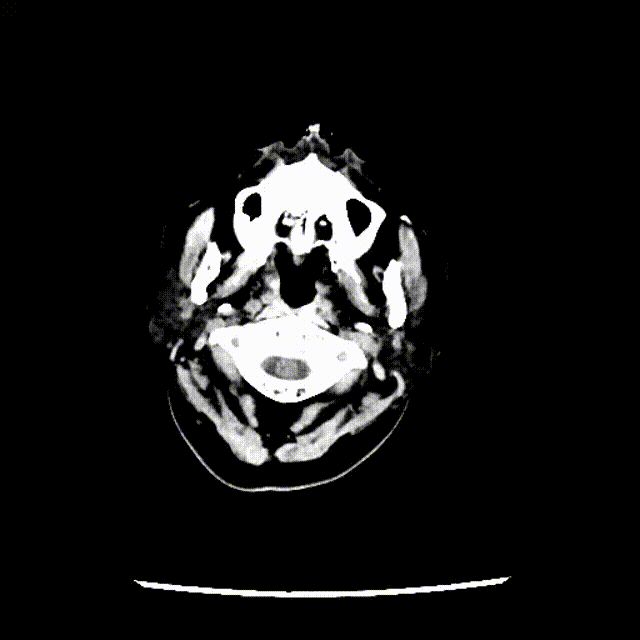

复查头颅CT提示广泛蛛网膜下腔出血,脑室扩张。基底动脉远端扩张请结合临床。急诊CTA提示:基底动脉两枚动脉瘤(图1)。

入院后立即行脑血管造影提示椎基底冗长扩张(基底动脉脑桥部分最宽处约5.2mm),伴有基底动脉多发动脉瘤,基底动脉尖动脉瘤(最大径约8mm)伴子囊和基底动脉下段动脉瘤(最大径约11mm)(图2)。